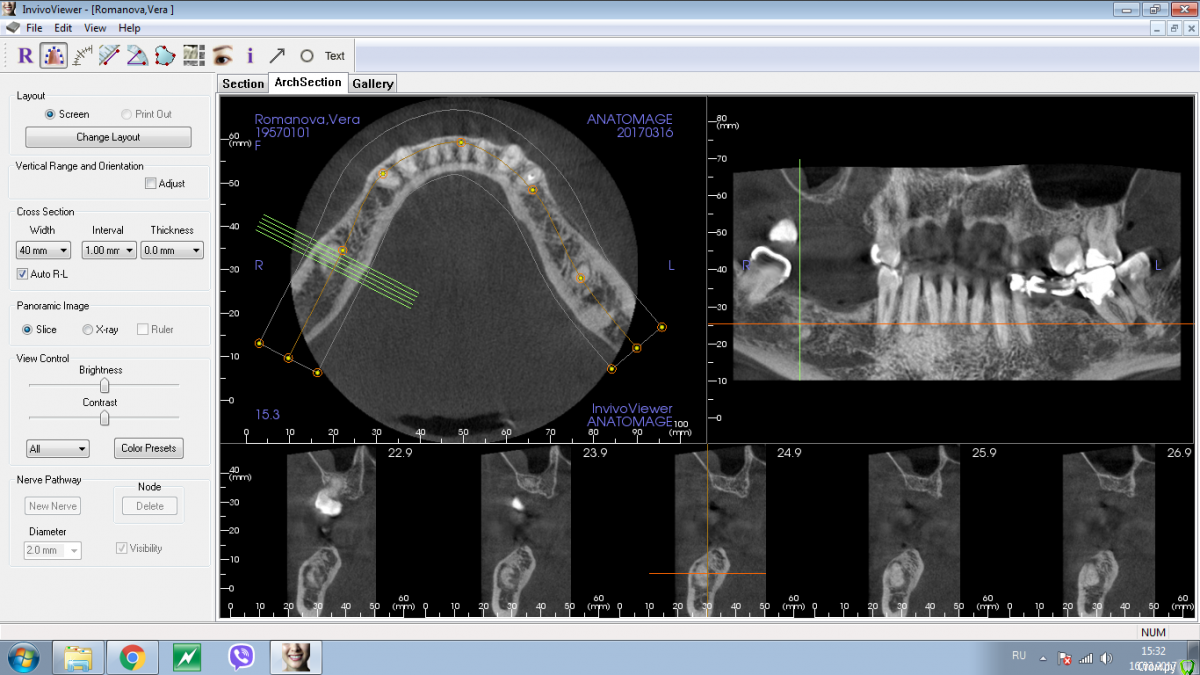

Shakirbura Опубликовано 18 марта, 2017 Поделиться Опубликовано 18 марта, 2017 Здравствуйте, коллеги!Пациентка обратилась по поводу протезирования на имплантатах. На снимке обнаружил вот такое образование. Раньше не встречал. Какими должны быть мои действия в таком случае?Спасибо! Ссылка на комментарий

Andrey Shiryaev Опубликовано 18 марта, 2017 Поделиться Опубликовано 18 марта, 2017 Похоже на остеому. Ссылка на комментарий

Kovalov Igor Опубликовано 19 марта, 2017 Поделиться Опубликовано 19 марта, 2017 Конденсирующая остеома.Покажите на Фейсбуке Рогацкину Дмитрию , читал что ставят прям в остеому Ссылка на комментарий

Карен Аванесов Опубликовано 19 марта, 2017 Поделиться Опубликовано 19 марта, 2017 Аккуратно убрать, поставить имплантат, при необходимости графт, если это остатки зуба будет видно. если нло на гистологию. Ссылка на комментарий